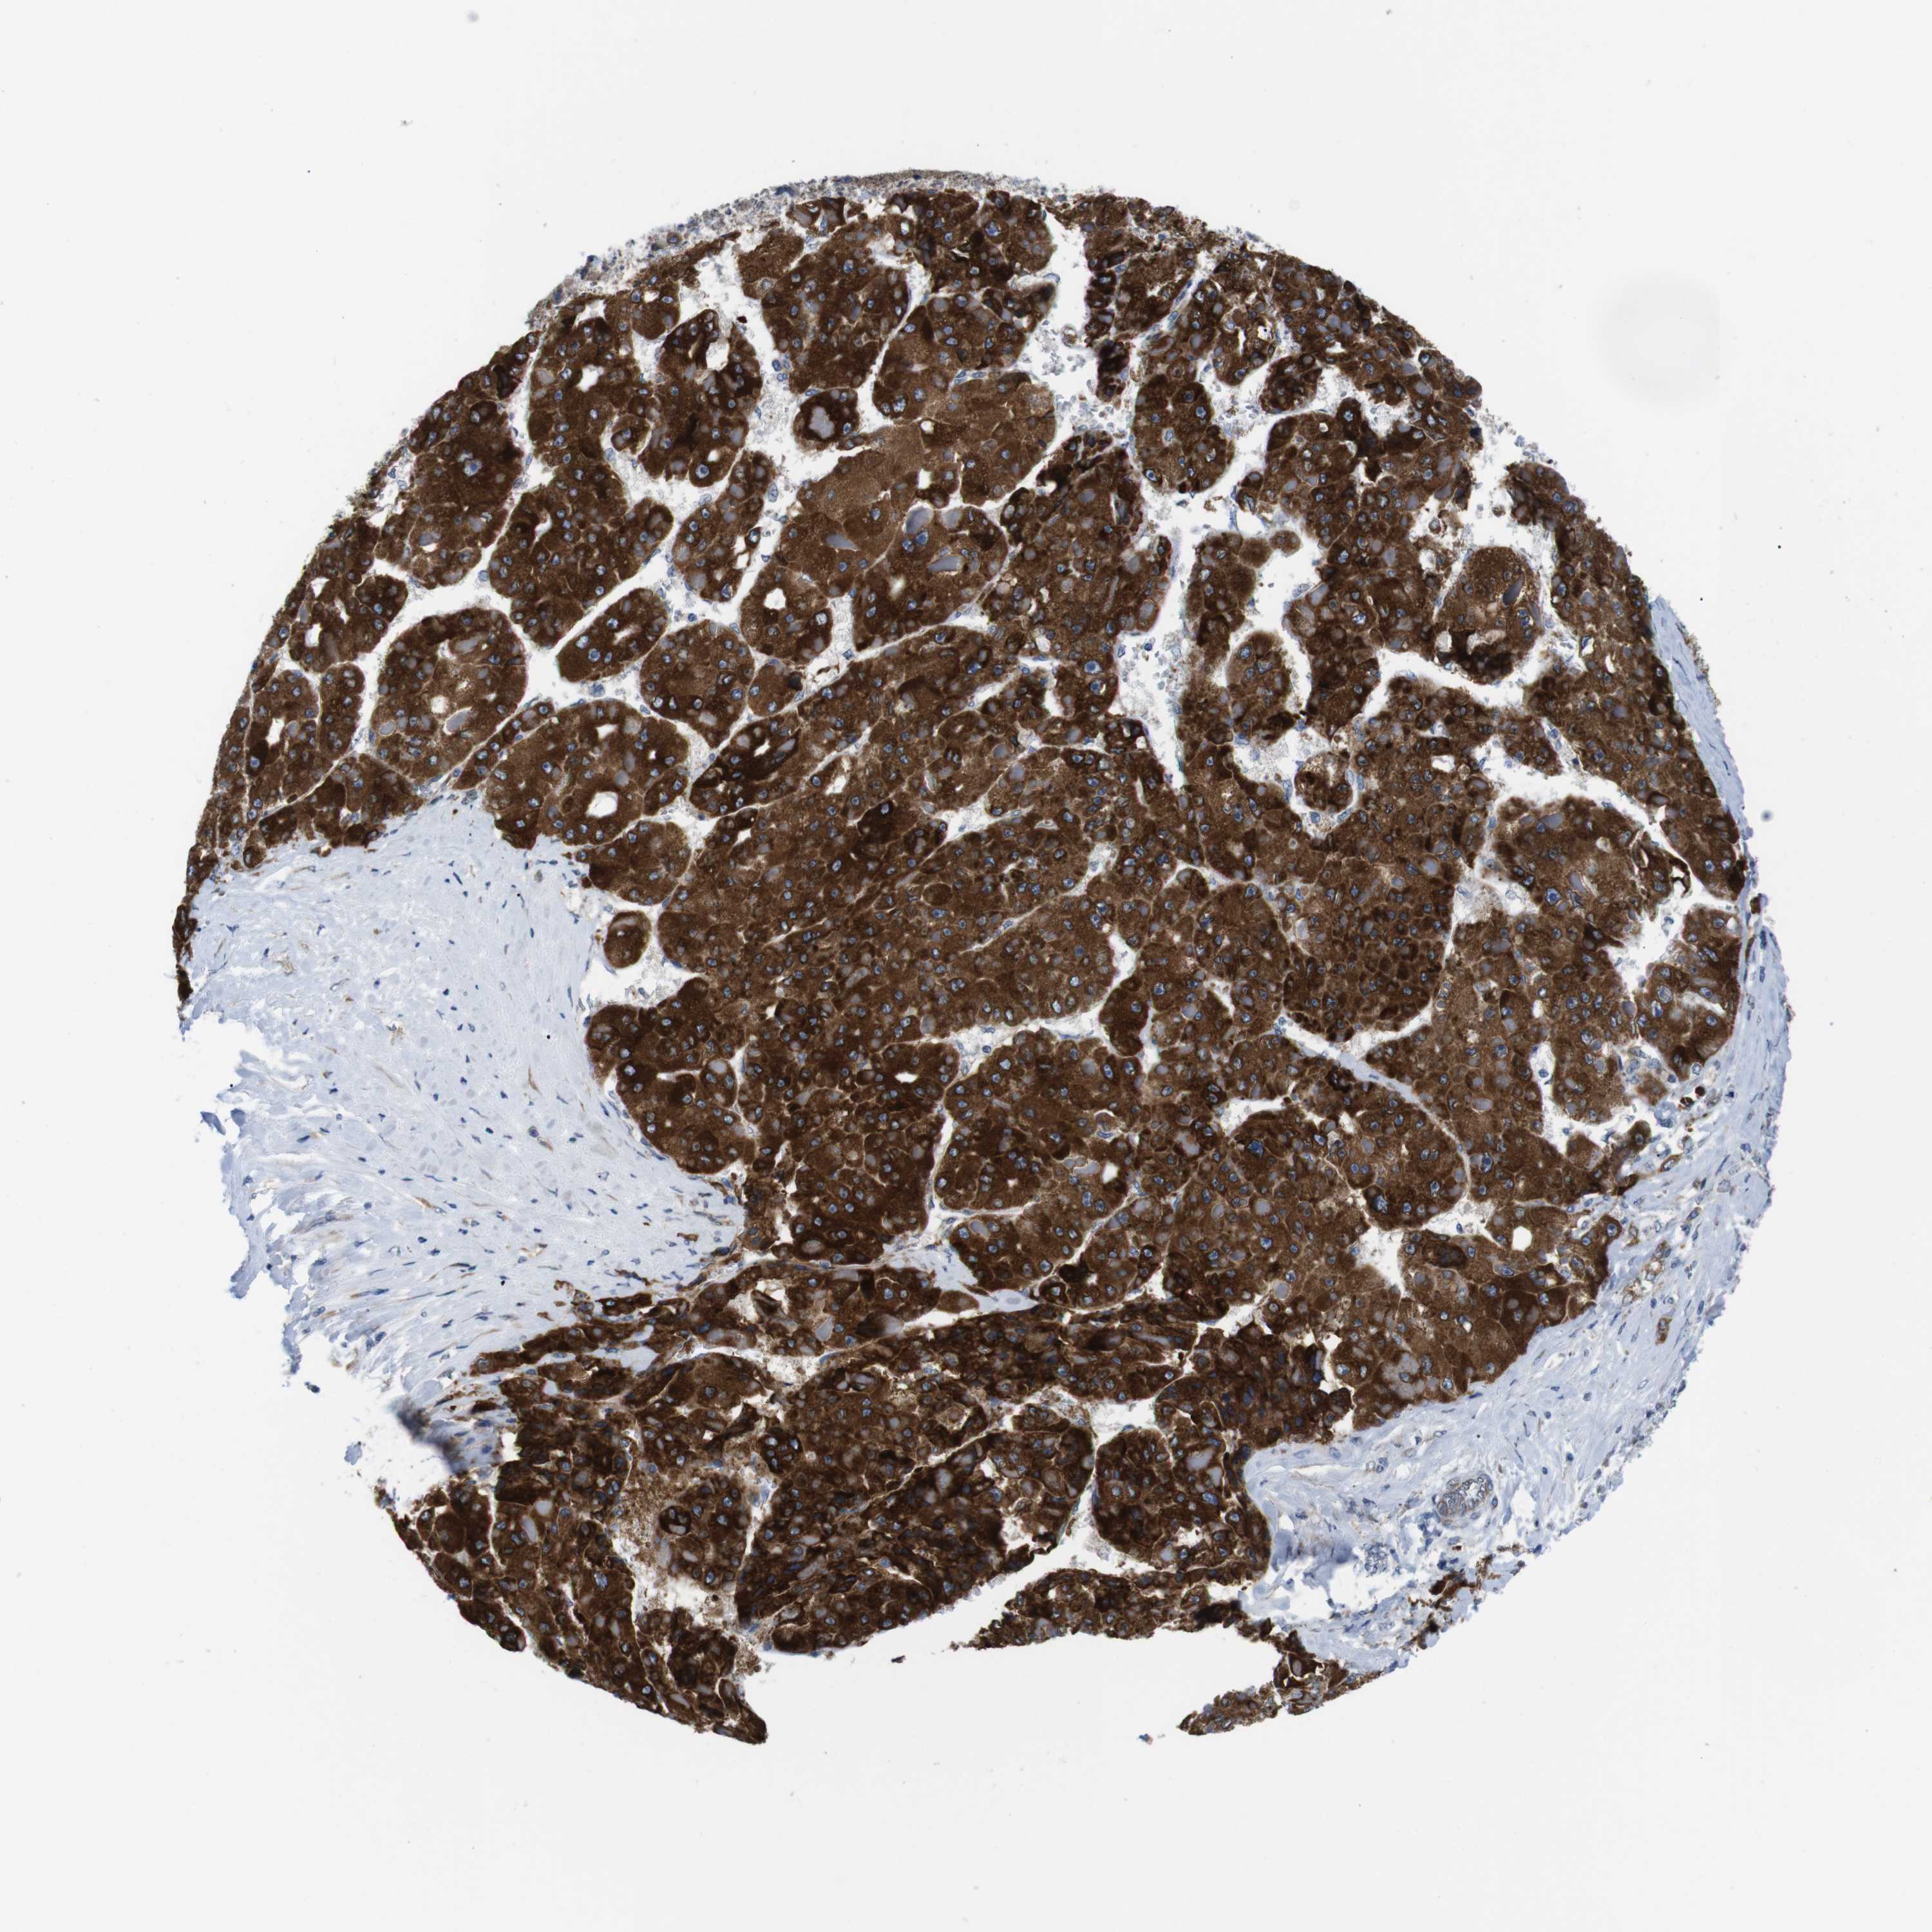

LIVER CANCER - Protein expressioni

A mouse-over function shows sample information and annotation data. Click on an image to view it in a full screen mode. Samples can be filtered based on level of antibody staining by selecting one or several of the following categories: high, medium, low and not detected. The assay and annotation is described here.

Note that samples used for immunohistochemistry by the Human Protein Atlas do not correspond to samples in the TCGA dataset.

Antibody stainingi

Antibody staining in the annotated cell types in the current human tissue is reported as not detected, low, medium, or high, based on conventional immunohistochemistry profiling in selected tissues. This score is based on the combination of the staining intensity and fraction of stained cells.

Each image is clickable and will lead to virtual microscopy that enables deeper exploration of all samples and also displays staining intensity scores, fraction scores and subcellular localization as well as patient and tissue information for each sample.

Antibody HPA014837

Staining

High

Medium

Low

Not detected

Intensity

Strong

Moderate

Weak

Negative

Quantity

>75%

75%-25%

<25%

None

Location

Nuclear

Cytoplasmic/membranous

Cytoplasmic/membranous,nuclear

Cholangiocarcinoma

Carcinoma, Hepatocellular, NOS